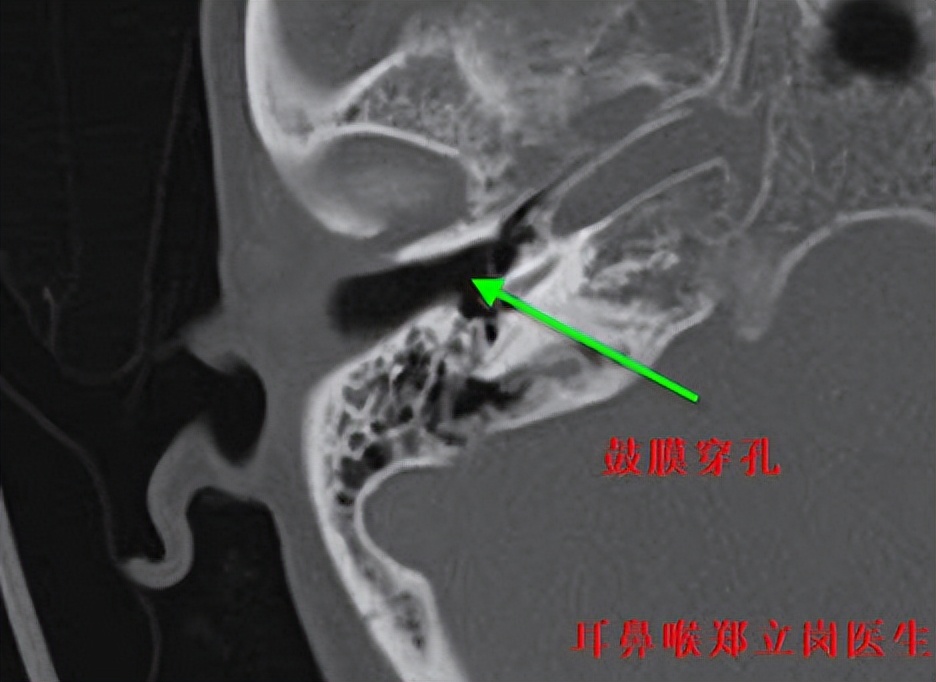

患者黄,女,62岁,广西南宁青秀人。患者右侧鼓膜大穿孔,鼓室中有肉芽组织,这次是专门从广西过来做耳内镜中耳炎微创手术的。

插管全麻后就开始了手术,在耳内镜下不用做任何的体表切口,直接翻起外耳道鼓膜皮瓣,可见鼓室中两个肉芽,予以清理后听骨链是完整的,活动可。取合适大小的耳屏软骨修剪后修补鼓膜,鼓膜修补好后检查了两遍确认没问题后就结束了手术。整个手术用时约50分钟,非常的顺利。术后查房患者无明显的不适,无手术相关的并发症。